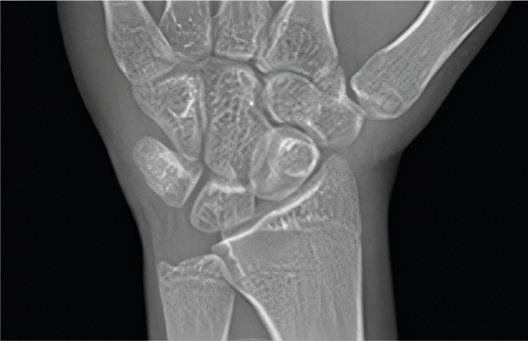

• Closed Growth Plate